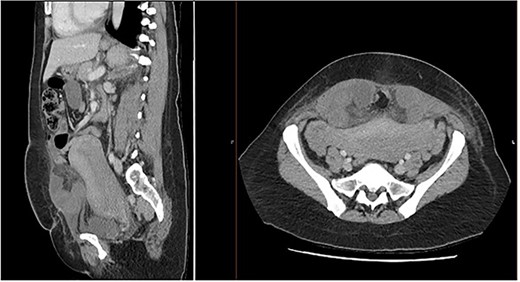

She had ongoing abdominal pain following her LSCS, which became severe on day 4 with associated bilious vomiting. The general surgical team was consulted. On examination, she was haemodynamically stable and afebrile, was writhing in the bed in pain and was firmer in her left and right lower quadrants with marked tenderness in comparison to upper quadrants on abdominal examination. Her serology was unremarkable. An urgent computed tomography (CT) abdomen pelvis demonstrated a 25 mm transverse defect in her posterior rectus sheath containing multiple loops of small bowel with submucosal and mesenteric oedema and free fluid within the hernial sac. The appearance was in keeping with a strangulated interparietal hernia containing small bowel (Fig. 1).

Sagittal and axial CT abdomen and pelvis slices demonstrating oedematous small bowel loops herniating between layers of the anterior abdominal wall.